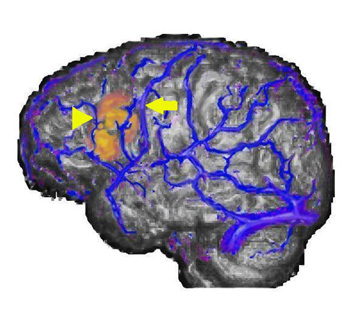

27-year-old right handed woman who underwent MRI and MRV to rule out a structural lesion. The patient volunteered to perform a verb generation task.

The image shows the fusion of three different procedures. In gray scale is the volumetric rendition of the brain obtained from the MRI sequence. In blue are depicted the surface veins and sinus of the left hemisphere from the MR-venogram. In yellow and red appears activation obtained from the echo-planar sequence used for functional MRI.